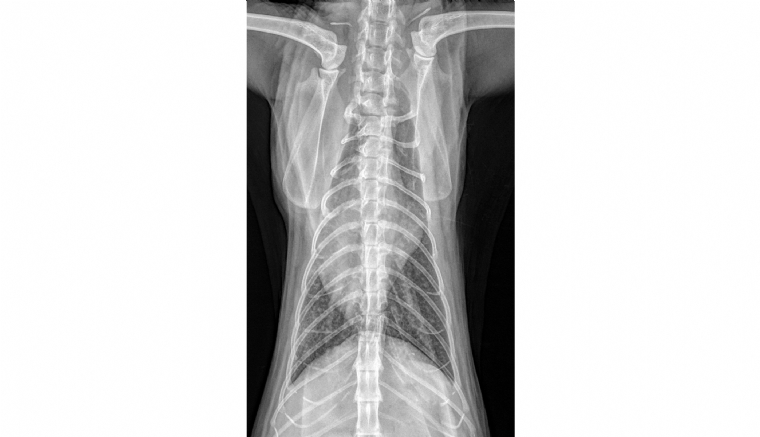

Mercredi 26 Août 2020 Animaux de compagnieVues ventrodorsale et latérale droite du thorax.

Un chat européen de 11 ans est présenté pour l'exploration d'une dermatite squameuse généralisée associée à une dégradation progressive de l'état général et une fatigabilité.